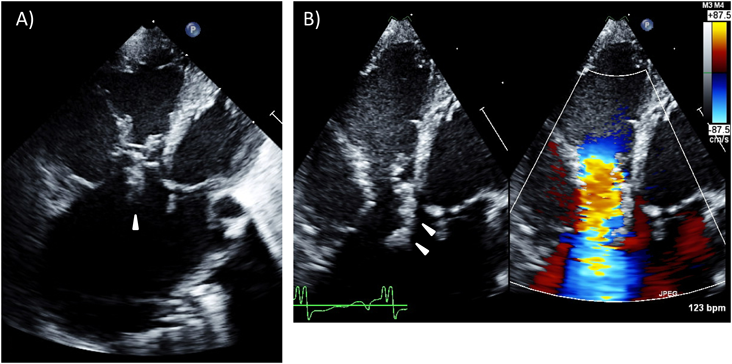

(2) 三尖弁異形成(tricuspid valve dysplasia)(Fig. 12)

Pediatric Cardiology and Cardiac Surgery 33(2): 140-156 (2017)

Fig. 12 Congenital tricuspid valve dysplasia

(A) Apical four-chamber view of tricuspid valve dysplasia. Note the significantly enlarged right ventricle and atrium. The arrowhead indicates the accessory tissue of the tricuspid valve. (B) There is a huge coaptation gap in the center of the tricuspid valve, where a massive regurgitation jet originates.

三尖弁の構成要素である弁葉,腱索,乳頭筋のいずれかの構造異常により三尖弁閉鎖不全を来している病態を指す20).弁葉の異常としては,弁尖肥厚や部分的な弁組織の欠失が起こりうるが,短腱索によるtethering等の弁下組織の異常も同時に合併することが多い.機能的弁輪(ヒンジ部)の位置異常がないことでEbstein病とは鑑別される.